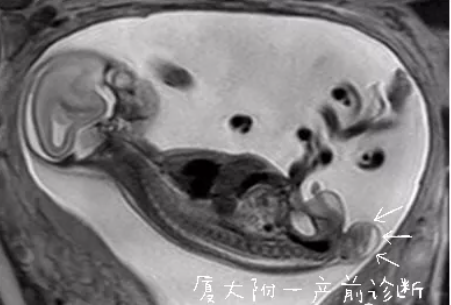

经过厦门大学附属第一医院

产前诊断医生初步判断

这是胎儿骶尾部畸胎瘤

是小儿常见实体瘤之一,好发育身体中线及其两旁,由三胚叶组织构成。以骶尾部畸胎瘤最多见,它可发生在任何年龄,以小儿,尤其是新生儿及婴儿期最多见。骶尾部畸胎瘤的产前诊断率可达90%以上。其病理性质有良恶性之分,绝大多数新生儿骶尾部畸胎瘤为良性肿瘤。

厦门大学附属第一医院产前诊断多学科专家团队,全面分析了胎儿可能的病情变化趋势及不良预后。郑女士和家属听从了医生的建议,实行了介入性产前诊断羊水穿刺,结果正常。由于宝宝属于胎儿骶尾部畸胎瘤(I型),80%预后良好,勇敢的父母选择继续妊娠。